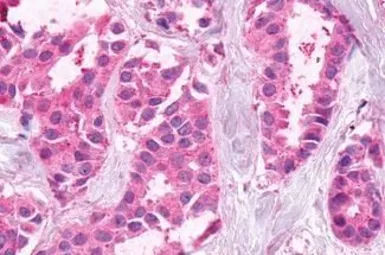

XPR1 antibody

Cat. No. GTX13290

ApplicationsICC/IF IHC-P

ReactivityHuman, Mouse, Rabbit, Hamster, Monkey